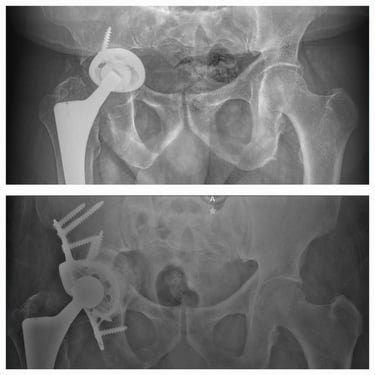

Cirugía de revisión de cadera y rodilla.

Casos complejos y manejo de complicaciones de cadera y rodilla

Manejo de secuelas y complicaciones de prótesis de cadera y rodilla.